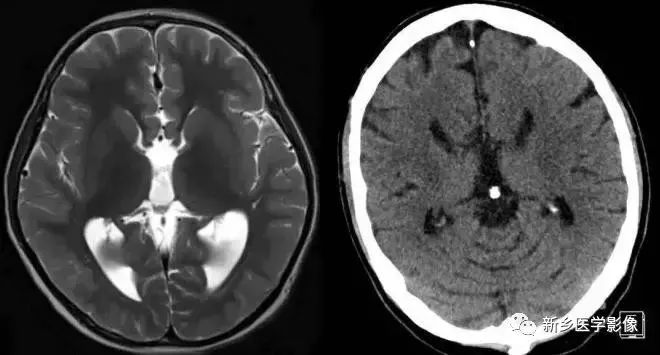

❻ 孤立性第四脑室

当导水管和第四脑室出口严重狭窄或完全阻塞时,四脑室则被孤立起来,这种情况称为孤立性第四脑室。